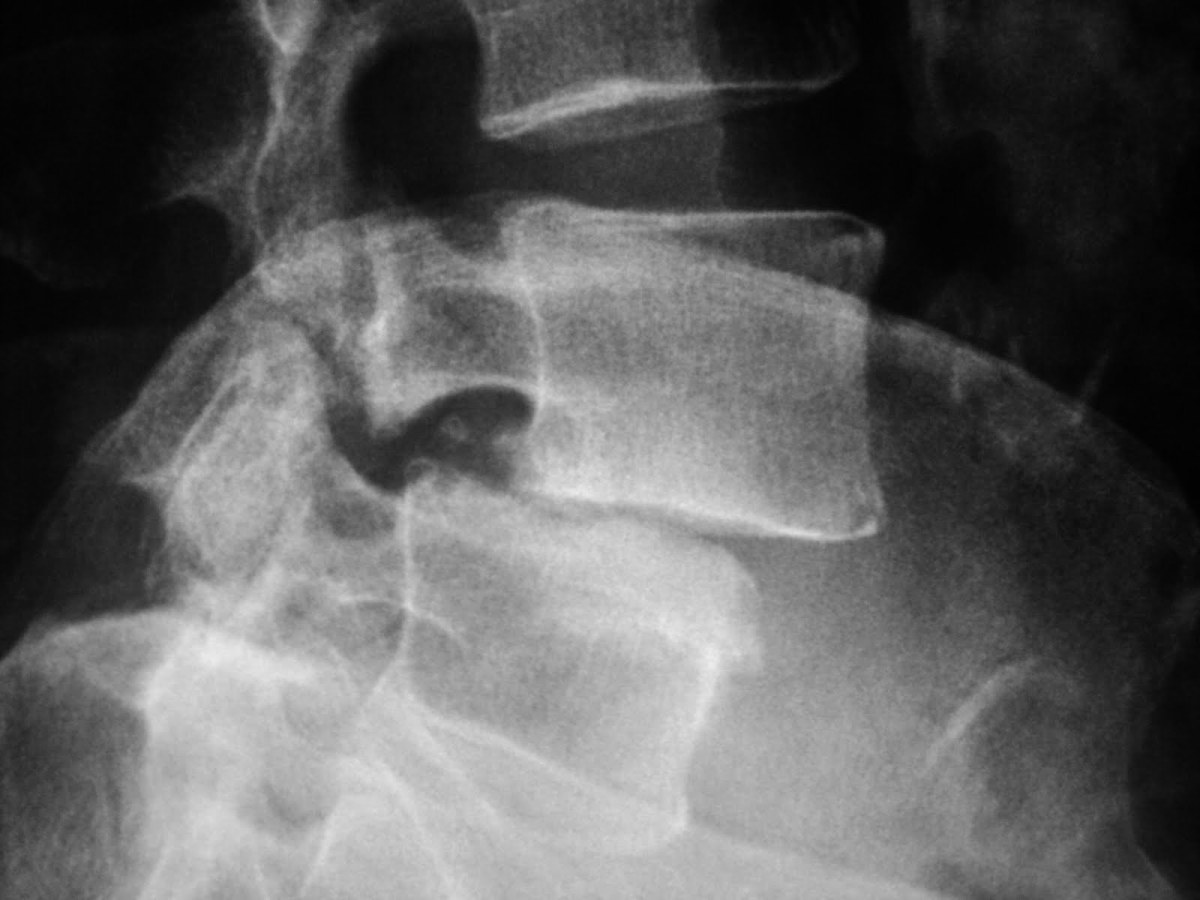

Lumbar Spine Radiography of a hospital patient Stock Photo Alamy Lumbar X Ray For Sciatica Sciatica, also called lumbar radiculopathy, is a pain that originates along your sciatic nerve. Learn about the signs, symptoms and causes of sciatica, a condition that affects the sciatic nerve in your lower back and leg. Sciatica is nerve pain from irritation or compression of the sciatic nerve or its branches. It can detect abnormalities, injuries, or diseases of the. Lumbar X Ray For Sciatica.